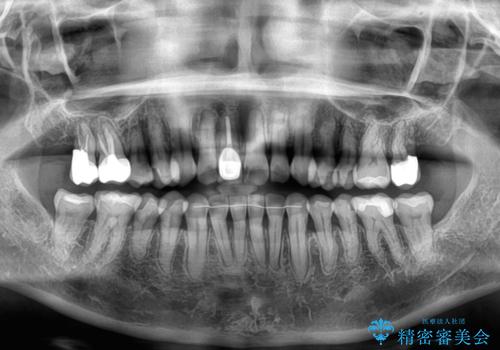

デコボコと銀歯 矯正治療とセラミック治療で綺麗な口元に

- 前歯のデコボコと口を開けたときに見える銀歯を気にして来院された患者様です。

ある程度デコボコが解消されれば大丈夫とのことで、インビザライン・モデレートパッケージを利用して歯列を整えて行くこととしました。

矯正治療後に銀歯をセラミッククラウンなどに置き換えていくと、どうしても後戻りを起こしてしまうため、矯正治療が概ね終了した時点で銀歯を全てセラミックとし、最後に仕上げでインビザラインにを用いて細かいデコボコを改善していくこととしました。